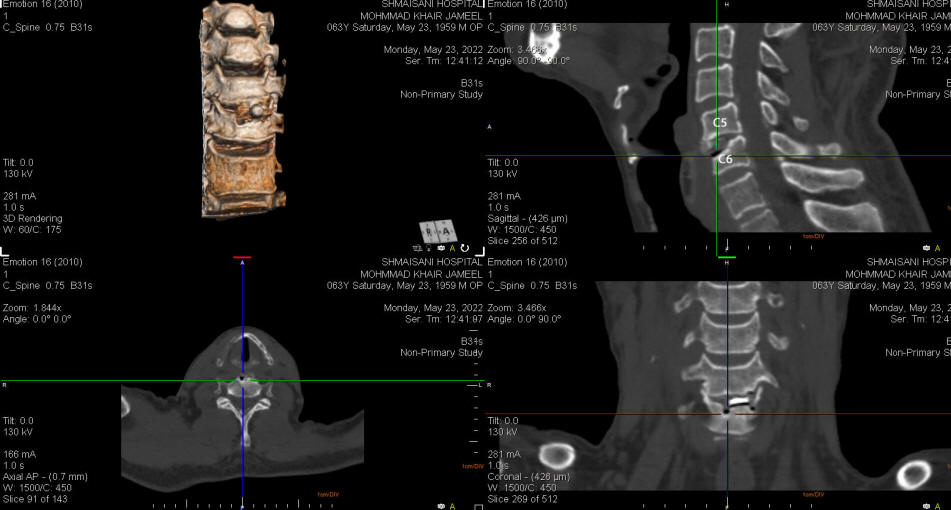

24-MAY-2022  MUHAMED KHEIR JAMEEL AL-BANADRAH  61 YEARS  CONDITION AFTER PERFORMED DISCECTOMY WITH SUBSEQUENT REACTION OF THE SPINAL CORD TO THE PEEK AND PUTY.

The patient was sent for investigations and dynamic studies of the cervical spine ruled out overmobility and CT-scan showed acceptable position of the construct. Lab investigations done and ESR was 95 mm/h and CRP was 11 mg/dL.

CT-scan reconstructed using ORS Visual to see the alignment. Dynamic studies also ruled mobility of the segment.